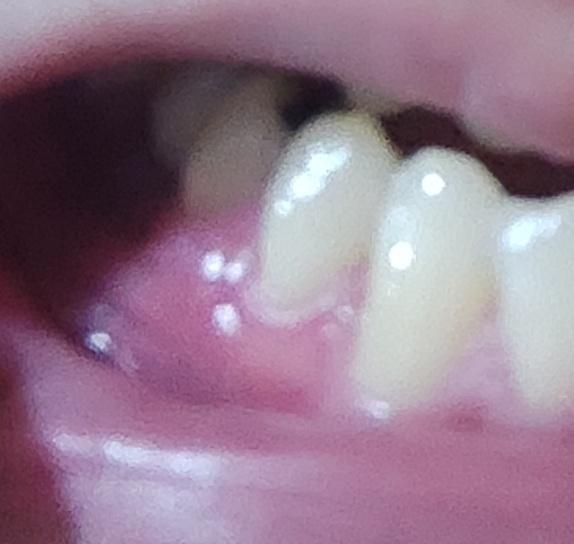

잇몸이 항상 좀 부어있는데 괜찮은 상태인가요?

잇몸이 계속 간지러운 느낌이 있고

특히 식사를 하고 나면 더 크게 붓는 경향이 있습니다

가끔 이쪽 치아가 찌릿한 느낌도 드는데 치과에선 여쭤봐도 별 말이 없네요 괜찮을까요?

• 1번 째 사진

사진상으로는 치아나 잇몸에 특별히 문제가 보이지는 않습니다. 교합이 강해서 그렇거나 식습관이 원인일 수도 있습니다.